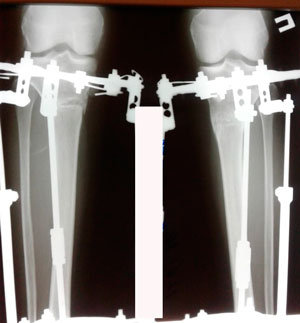

Пациентка - 37 лет.

Диагноз: варусная деформация голеней. Ротация с обеих сторон.

Дата операции - 24.10.2019г.